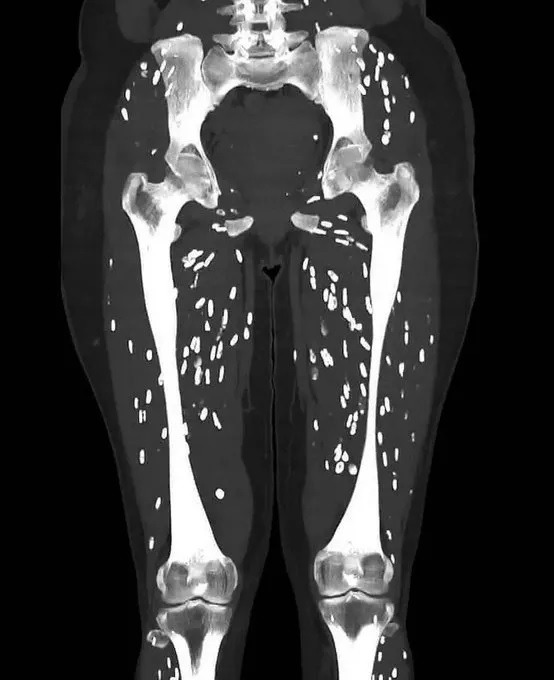

શું તમે જાણો છો કે કાચું પાકેલું માંસ ખાવુ તમારા હેલ્થ માટે કેટલું જીવલેણ સાબિત થઈ શકે છે. થોડા સમય પહેલા એક વ્યક્તિના મગજમાં કીડા હોવાનું સામે આવ્યુંહતું. ત્યારે હાલમાં જ ડો.સૈમ પોતાના સોશિયલ મીડયા પર સિટી સ્કેનને એક તસવીર મૂકી તો આખી દુનિયા હચમચી ગઈ. આ સિટી સ્કેલનમાં એક દર્દીના ઘૂંટણમાં જીવતા કીડા ફરતા જાેવા મળ્યાં. આ કીડાને કારણે દર્દીના શરીરમાં ઈન્ફેક્શન થઈ ગયું હતું. તેણે જણાવ્યું કે, તેણે ડુક્કરનું કાચું પકાયેલું માંસ ખાધુ હતું. જેનાથી તેના પગમાં જીવિત કીડા પેદા થયા હતા.

આ સ્થિતિને ઈન્ટેસ્ટાઈન ટૈનિયાસિસ કહેવાય છે. ડોક્ટરે જણાવ્યું કે, આવી સ્થિતિમાં દર્દીના મગજ સુધી કીડા પહોંચી શકે છે. જેનાથી દિમાગમાં સિસ્ટ બની શકે છે. આવામાં માથાનો દુખાવો કે અન્ય ગંભીર ન્યૂરોલોજિકલ સમસ્યાઓનો સામનો કરવો પડી શકે છે. વાયરલ સિટી સ્કેનમાં જાેઈ શકાય છે કે, ચોખાના આકારના કીડા વ્યક્તિના પગમાં ચાલતા દેખાય છે. આ કીડા ઘૂંટણની આસપાસ ફરી રહ્યાં છે.

સિસ્ટીસકોર્સિસ એક પેરાસાઈટ ઈન્ફેક્શન છે, જે પોર્ક કે ટેપવોર્મને કારણે થાય છે. આ ઈન્ફેક્શન ત્યારે થાય છે, જ્યારે ટેપવોર્મ લાર્વા વ્યક્તિના ટિશ્યુ સુધી ઈન્ફેક્શન કરે છે. જેનાથી શરીરમાં સિસ્ટ બની જાય છે. ઈન્ફેક્શન ત્યારે થાય છે, જ્યારે કોઈ વ્યક્તિ દૂષિત ભોજન કે પાણીનું સેવન કરે છે. જેમાં કીડાના ઈંડા હોય છે. આ ઈંડા પેટમાં લાર્વા બની જાય છે. લાર્વા માંસપેશીઓ, મમગજ, આંખ જેવા શરીરના ભાગો સુધી પહોંચી જાય છે. તેના બાદ લાર્વા સિસ્ટ બની જાય છે, જે શરીર પર સોજાનું કારણ બને છે.